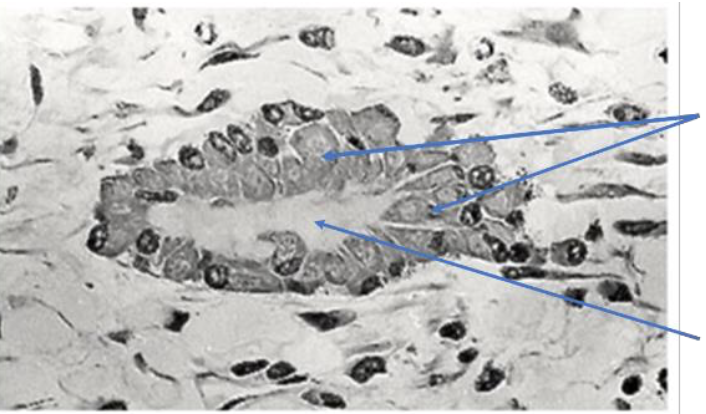

What do osteoblasts do?

Synthesise new bone, deposit osteoid

What is osteoid?

Matrix protein of bone: collagen, osteocalcin, osteopontin

Fill in the missing labels: